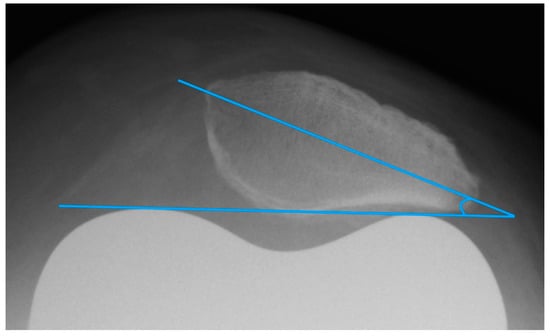

The patella tilt is believed to be involved in the development of anterior knee pain [9,14]. Grelsamer published a method for standardized measurement of the patellar tilt in 1992 [24]. On patella tangential X-rays, a line connecting the medial and lateral patellar poles is drawn and the angle between this line and a horizontal line is determined. However, this method is not very resistant to varying leg rotations. For this reason, the measurement of the patellar tilt according to Gomes [22] was used. It is largely similar to the method by Grelsamer, but instead of the horizontal it uses a line between the apices of the femoral condyles as femoral reference line (see Figure 4) [22]. Openings of the angle to the lateral are given with a positive sign, openings to the medial with a negative sign. Values up to ± 5° are considered to be normal [9].

2.3.4. Patellar Morphology

To ascertain the patellar shape type and to distinguish patellar euplasia from dysplastic variants, the patellar joint surface angle (facet angle) described by Christiani was measured. This angle is formed by the patella ridge and each the medial and lateral joint facet [25] (see Figure 6). On axial radiographs in 60° knee flexion, this angle should be between 120° and 139°. Values < 115° and ≥ 145° are considered as dysplastic [26].

Figure 4. Measurement of the patella tilt with the method of Gomes.

Figure 6. Measurement of the patellar facet angle with the method of Christiani. Additionally, the image shows an example of possible difficulties in determination of patellar facet tangent, in this case due to bony superimposition at the medial facet.